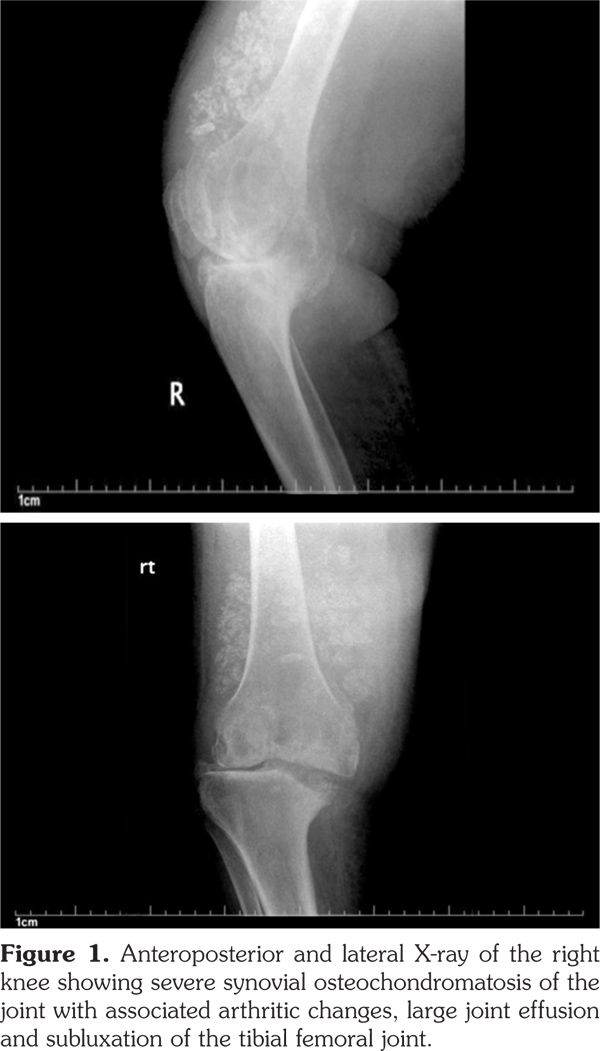

Plain radiographs of the knee joints revealed joint effusions with multiple rounded intra-articular loose bodies, erosions on the medial aspect of the tibial plateau, tricompartmental joint space narrowing, osteophytes, subchondral cyst formation, heterotopic bone formation, and lateral subluxation of the tibia on the femur (Figure 1, 2).